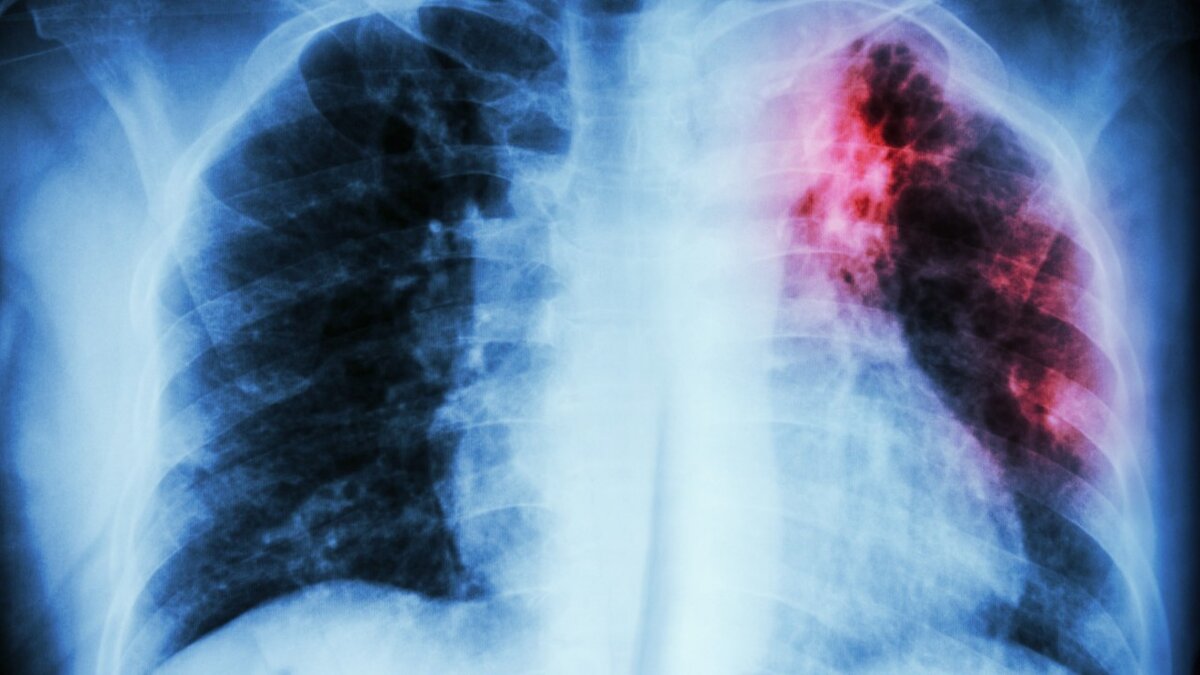

Прежде всего, хочу призвать граждан, чтобы они прислушивались к своему здоровью и берегли его. Если вы долго кашляете, плохо себя чувствуете, присутствуют слабость, потливость, потеря веса, не игнорируйте эти признаки. С этими симптомами стоит обратиться к врачу. Начать можно с терапевта, в нашей стране прописан четкий алгоритм обследования таких людей. Прежде всего, нужно сделать рентгенографию (флюорографию) и сдать анализ мокроты (если мокроты нет, ее получают специальной раздражающей ингаляцией). В 90% случаев это позволяет поставить правильный диагноз. Хочу особо отметить, что эти обследования просты и доступны пациентам и в районных поликлиниках. Но и наш РНПЦ тоже открыт для всех. Если человек хочет, он может обследоваться и у нас, есть и платный, и бесплатный прием. В зависимости от ситуации мы помогаем всем обратившимся.